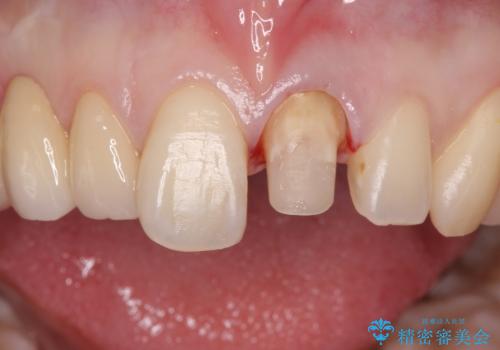

前歯を綺麗にしたい ジルコニアクラウンでの治療

- 前歯の被せ物のやり替えを希望して来院されました。

再根管治療の後、審美性の良いジルコニアクラウンをセットしていきます。

歯ぐきの状態も良く、適合の良い被せ物を入れることができました。

審美性もかなり改善され、大変喜んでいただけました。